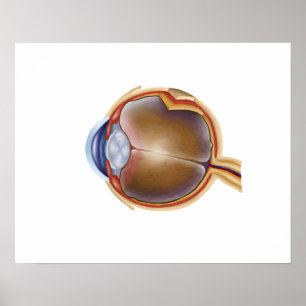

Poster Anatomia Do Olho Humano

Preço31,35 €